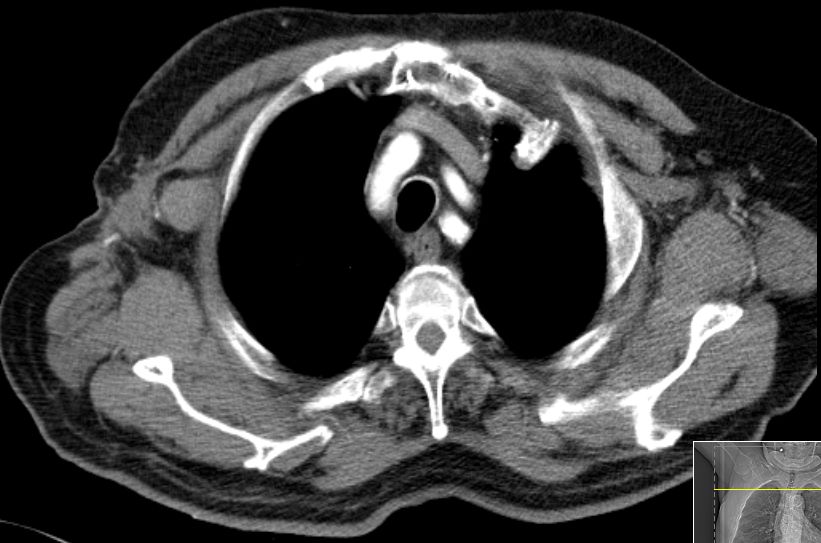

84-jährige Frau, die vor 3 1/2 Jahren einen 35 mm großen derben

Rektumpolypen entwickelte. Die submuköse Exzision ergab ein malignes Melanom

mit Infiltration der tiefen Muskulatur und Ummauerung größerer Gefäße. BRAF+.

Vor 2 Jahren Rektumschleimhau-Rezidiv und Metastase rechts pararektal:

anteriore Rektumresektion. Vor 4 Monaten Lungenmetastase und singuläre

Hirnmetastase re occipital. Dabrafinib + Trametinib nach 2 Zyklen wegen

Hepatotoxizität und Hautausschlag abgebrochen. Jetzt: RT der Hirnmetastase

und des pararektalen Tumors. |